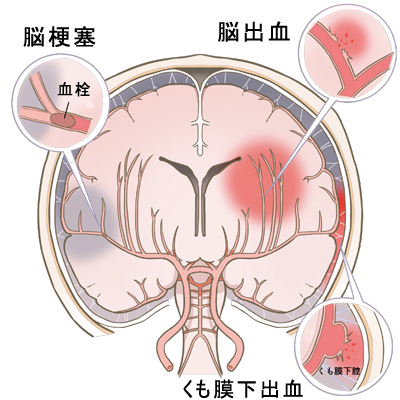

【脳卒中(脳血管障害)】

脳卒中(脳梗塞、脳出血、くも膜下出血)は、日本人の死亡原因第4位の疾患ですが、臓器別の死亡原因第 1 位、重度障害の原因疾患第 1 位で、現在の高齢化社会にあっては、医学的・社会的に非常に重要な疾患となっています。

脳卒中は重篤な疾患ですが、最新の画像診断と、遺伝子組換え組織型プラスミノゲン・アクチベータ(rt-PA)による薬物血栓溶解療法、脳神経外科手術、更にはここ数年で急速な進歩を遂げている脳神経血管内治療を、効率的に駆使することができれば、『脳卒中は “ 崖っぷちから救える疾患 ” 』となってきました。

高度脳卒中医療を行うためには、最新の医療設備と脳卒中関連領域の専門医チームによる連携診療体制が必須となります。当院では、24 時間稼働するCT/MRI脳・脳血管診断装置、24 時間対応可能な 血栓溶解療法(rt-PA 治療)、脳血管内治療と脳神経外科手術治療、そして 20 名余からなる脳卒中関連専門医(神経内科専門医、脳神経外科専門医、脳卒中専門医、脳神経血管内治療専門医、脳卒中外科手術技術指導医)が、効率的に脳卒中超急性期医療連携を行う体制が整っており、脳卒中患者さんの救命と後遺障害の低減、そしてリハビリテーション医師・理学療法士による神経機能回復治療を行うことができます。

当院は2020年9月に高度脳卒中センターを開設し、24時間365日脳卒中関連専門医による迅速かつ効率的な高度脳卒中医療を提供しており、良好な治療成績を得ております。

| 脳梗塞 | 脳出血 | くも膜下出血 |